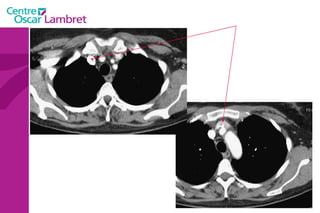

Le cœur  se situe au milieu du thorax, sur le diaphragme, la pointe tournée vers la gauche. L’appareil circulatoire

L’appareil circulatoire Le coeur  est un organe formé essentiellement d'un muscle, le myocarde, lequel est entouré d'un "sac" séreux, le péricarde et tapissé à l’intérieur par une fine membrane, l'endocarde.

Le coeur  comprend quatre cavités :  deux cavités droites, formées par l’oreillette (ou atrium) et le ventricule droit.  deux cavités gauches, formées par l’oreillette (ou atrium) et le ventricule gauche.  Les cavités droite et gauche sont totalement séparées par une cloison (septum).  Ces cavités sont connectées à des veines et des artères qui conduisent le sang venant ou partant du coeur.  L’appareil circulatoire